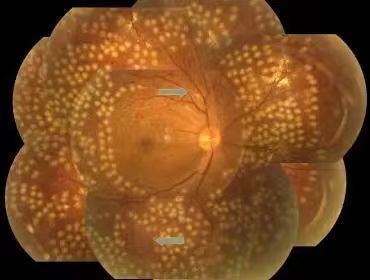

激光光凝治疗

全视网膜激光光凝术后